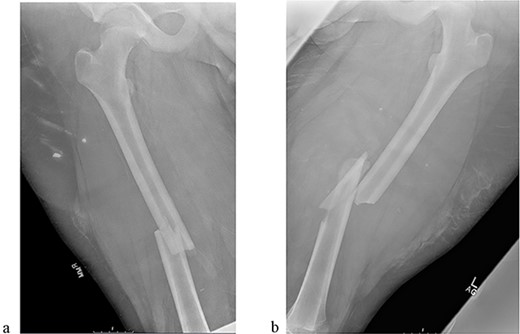

A 14-year-old boy sustained closed right and left mid-shaft femur fractures (Right OTA 32-A3, Left OTA 32-B2) after an all-terrain vehicle accident (Fig. 1a and b). The patient was classified as obese with a BMI of 37. Bone age was determined to be approaching skeletal maturity and so a rigid trochanteric entry femoral rod was selected for the implant [15, 16] (Fig. 2). Laboratory derangement included hyperphosphatemia and hypoalbuminemia. Therefore, additional measures to include early fracture stabilization and the RIA adjunct was selected for our patient [17].

(a) Right femur fracture (OTA 32-A3). (b) Left femur fracture (OTA 32-B2).